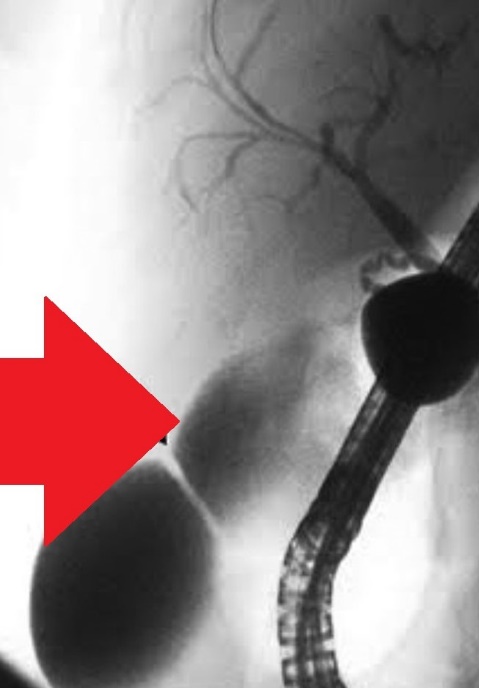

Percutaneous transhepatic cholangiography. Cystic dilatation of intrahepatic biliary duct with mucinous content (Courtesy Dr. V. Penopoulos)